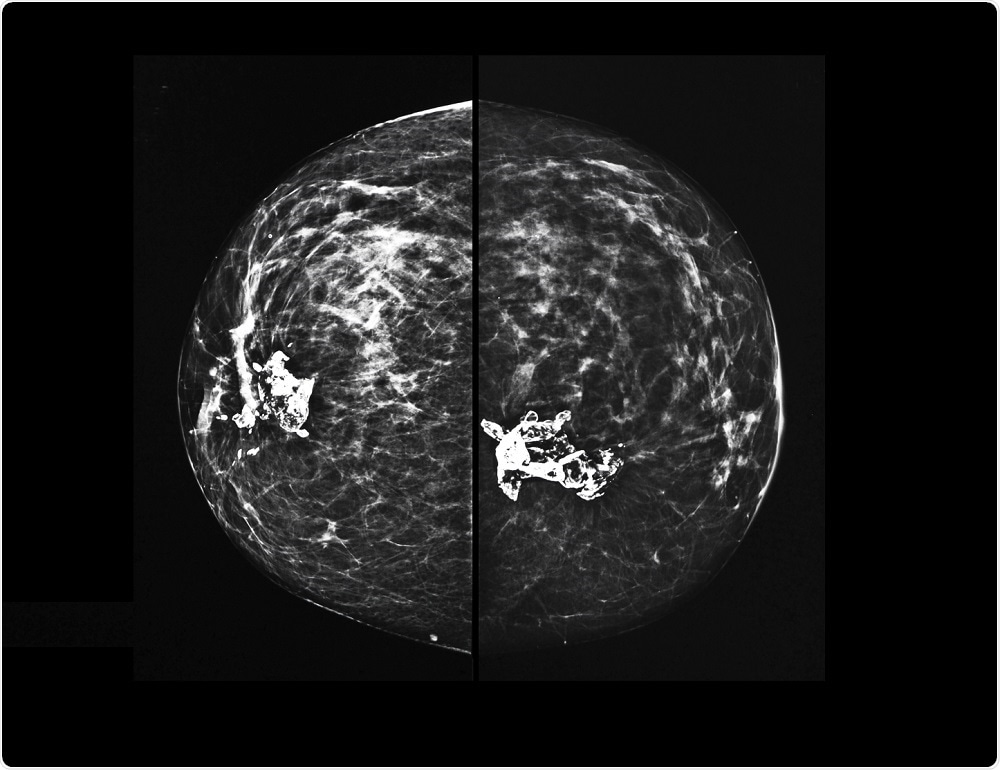

X-ray mammography of breast tissueSemnic | Shutterstock

A 2D mammogram, widely used for over a decade, is an X-ray of the breasts that is able to identify cancerous growths when they are too small to see or feel. During a mammogram, each breast is compressed by a clear plate and X-ray images are taken from two angles, the front and side of the breast.

DBT, commonly known as 3D mammography, takes X-ray images of the breast from several angles and builds a 3D image of the breast. It is reported to have a lower recall rate and a better ability to detect cancer when compared with 2D mammography.

In DBT, the X-ray moves in an arc over breast after it is compressed and captures images from several angles. These images are then digitized and synthesized into a 3D image of the breast.